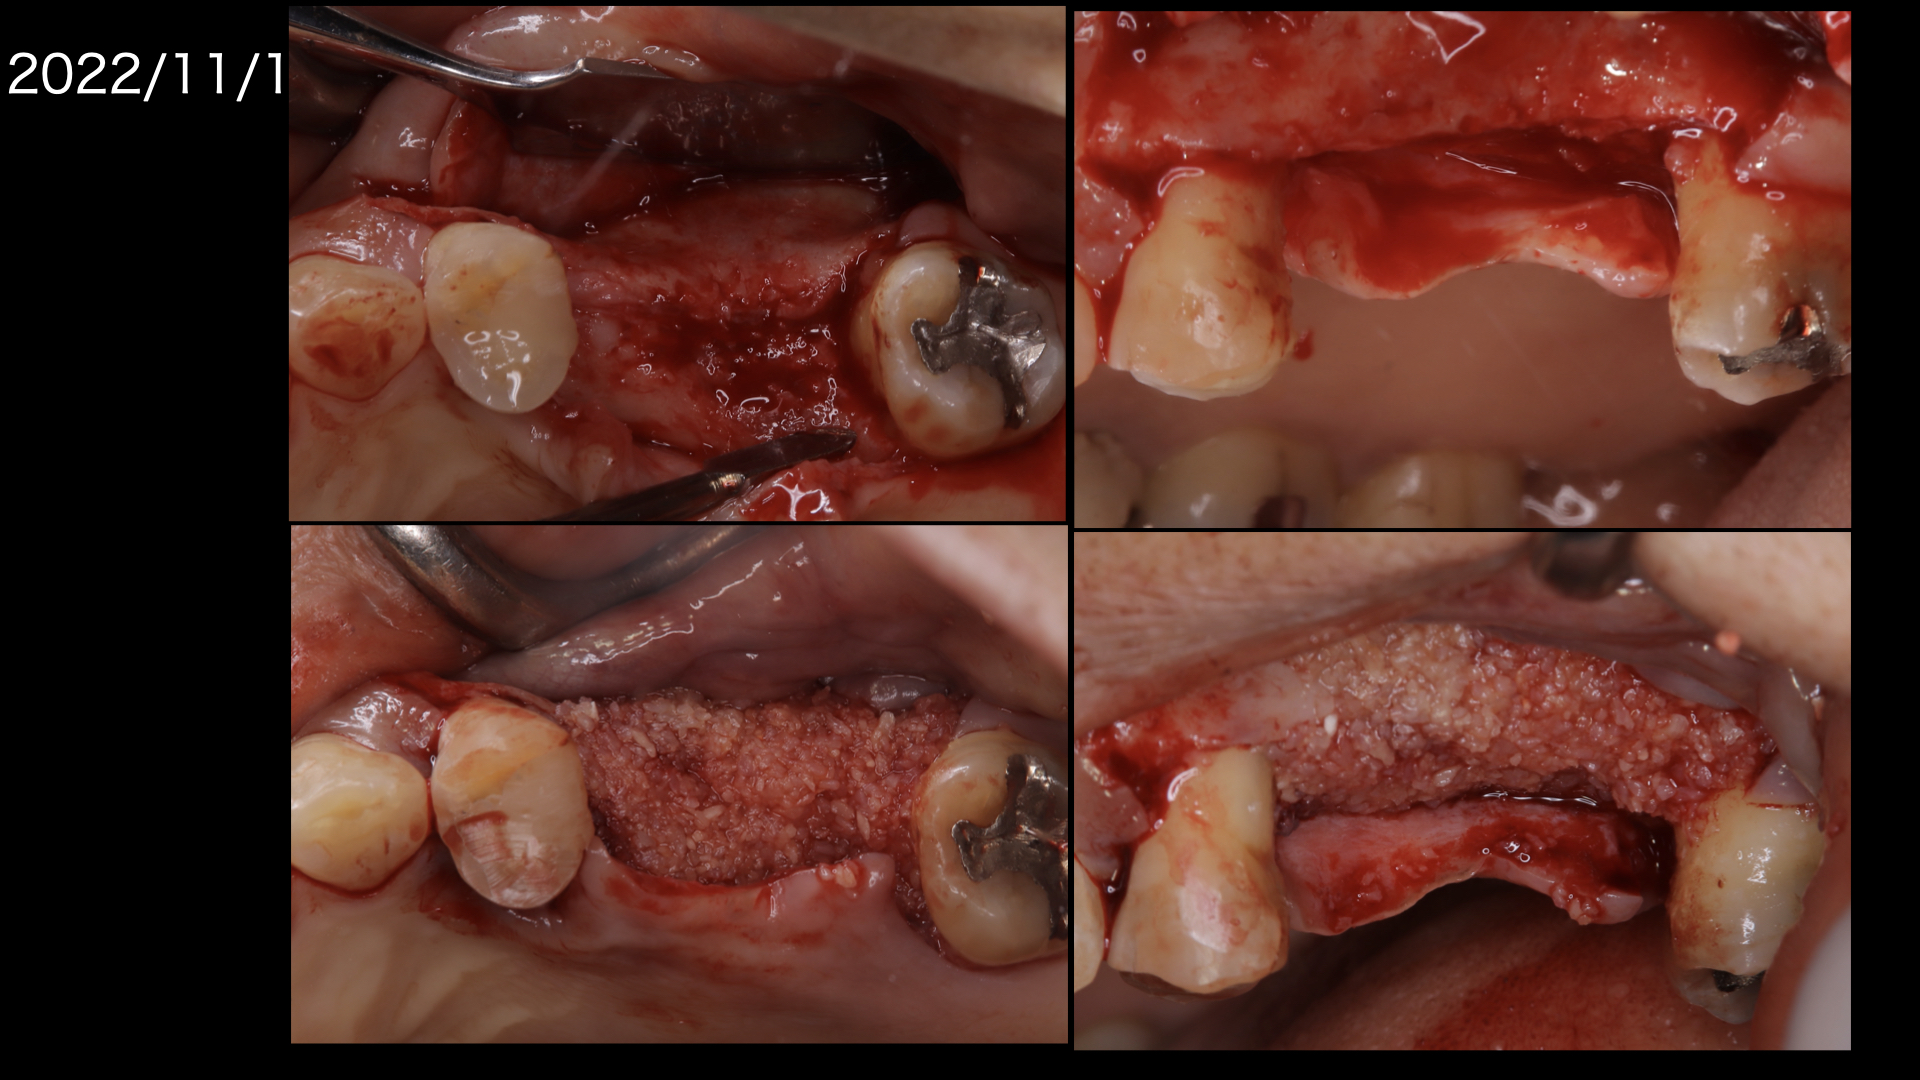

もともと歯周病で骨が吸収していましたので、この部分にインプラントをおこなうには骨を造らなければなりません。

骨造成。またこの部分は上顎洞にも隣接しているので、上顎洞挙上術も必要です。

骨造成と上顎洞挙上術を同時に行いました。

骨造成したので、歯肉をかなり減張切開する必要がありました。

上の図:減張切開したため、頬側に角化歯肉が喪失しておりこのままでは歯ブラシがしにくい状態です。

下の図:口蓋側から歯肉を移植しました。(遊離歯肉移植:FGG).頬側の歯肉の形態がよくなりました。